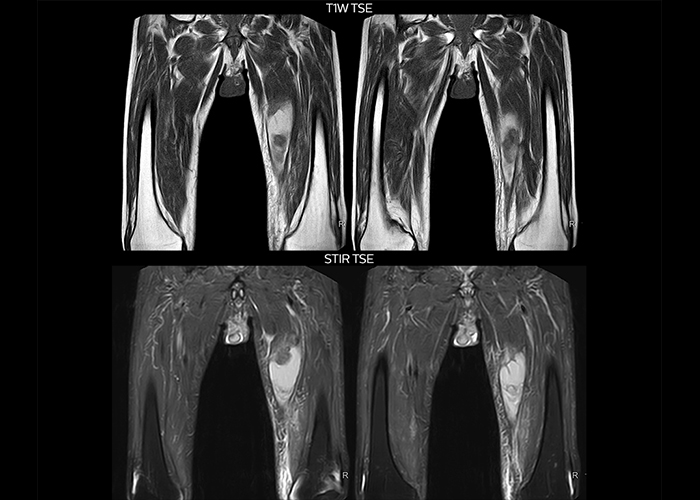

“On average, we scan about 80 patients per day, but on some days we scan well over 100 patients. The scanner is in use 7 days per week, operated 20 hours per day on week days and 8 hours per day in the weekend,” Mr. Tuna says. “To avoid coil changes we plan examinations of similar anatomies back to back, such as head and spine. Multiva helps us here a lot because coils don’t need to be changed frequently. Moreover, thanks to parallel imaging technology and 16-channel HeadSpineTorso and 8-channel MSK coils we are able to achieve excellent image quality. In this way Multiva helped us to increase both image quality and productivity.” “Neurological cases, such as brain and spine imaging, represent the largest share in our MR scanning, followed by musculoskeletal cases. In general, we use simple and basic imaging protocols. But occasionally, we use advanced techniques for problematic cases if necessary.

“Since we have Multiva, we have improved our workflow, because it has been so easy for our operators to learn and use Multiva. Our operators notice that the coils are lightweight and coils don’t need to be changed frequently. The user interface is easy to use. Features like this help us to scan a high number of patients. For instance, the musculoskeletal coils can be used interchangeably, and due to the user-friendly interface, the number of mistakes such as, for example, correct coil element selection has decreased significantly, because the system does it automatically by itself.” “Most important, Multiva satisfies our clinical imaging needs very well,” says Mr. Tuna. “Many features of Multiva have become similar to the Ingenia system. Even in more complex imaging such as abdominal and cardiac, the image quality and performance of Multiva is better than we expected. General surgeons and physicians from our hospital’s internal medicine department prefer to refer to us because of this.”